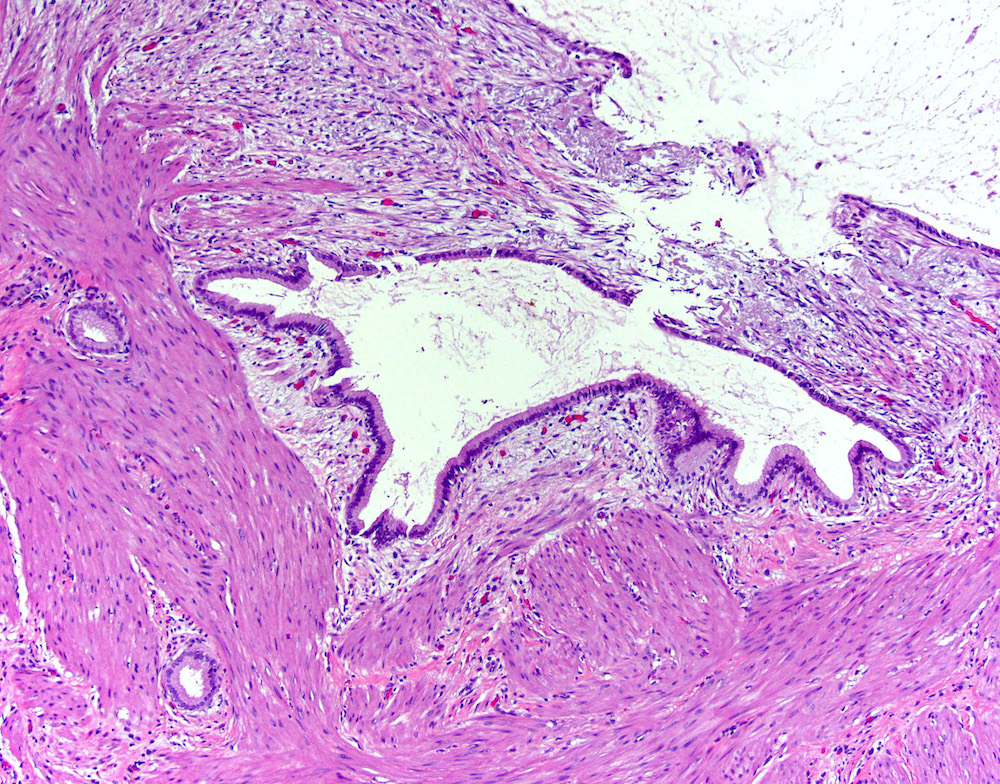

Microscopic (histologic) description

- Cystically dilated benign biliary glands accompanied by smooth muscle hypertrophy of gallbladder wall, thickened / fibrotic subserosa (StatPearls: Adenomyomatosis [Accessed 26 January 2021])

- Glands are distinct from the Rokitansky-Aschoff sinuses, which are epithelial diverticula, usually multifocal and occur throughout gallbladder secondary to injury, versus adenomyomatous nodule (distinct localized lesion of the gallbladder wall, 1 - 1.5 cm mural nodule in the fundus) (Am J Surg Pathol 2020;44:1649)

Microscopic (histologic) images

Contributed by Monica T. Garcia-Buitrago, M.D.